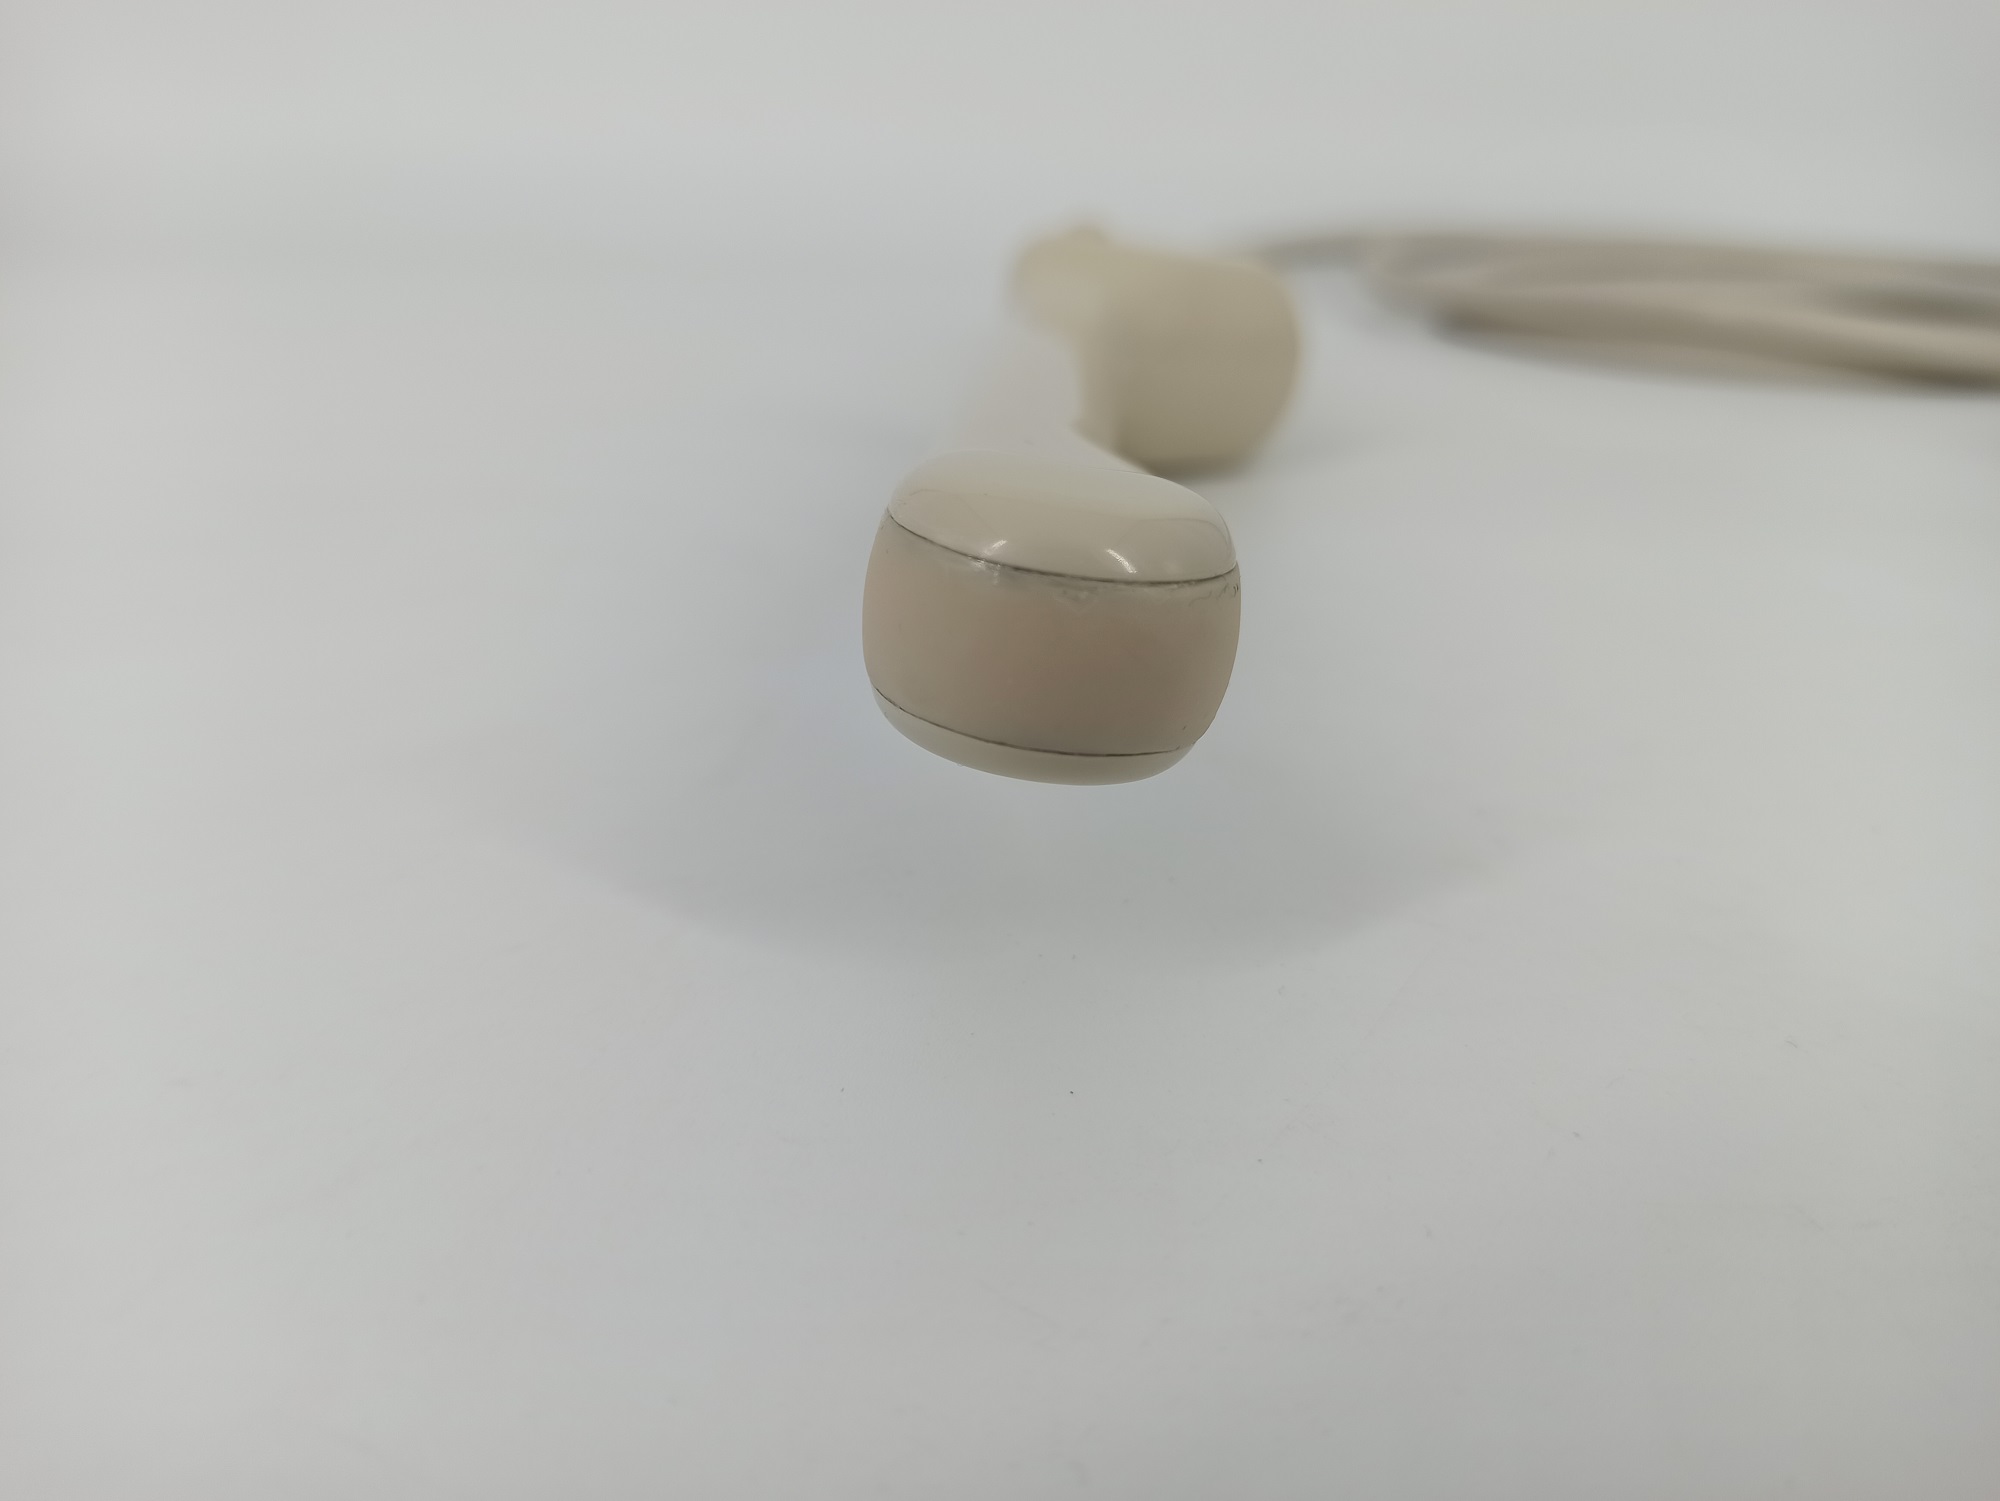

Hitachi EUP-V53W Endocavity Vaginal – HI VISION

Frequency Range: 8 – 4 MHz

Scan Width Convex: 10 mm Radius

Scan Angle Convex: 200° FOV

Hitachi EUP-V53W Endocavity Vaginal – HI VISION for Endovaginal